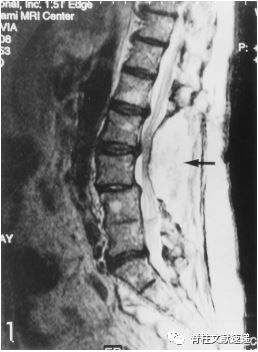

迟发性硬膜外血肿病例(箭头指示部分)

方法及结果: 在4018例患者中,有7例患者在术后3天以上出现硬膜外血肿。最初的症状包括严重的疼痛及四肢放射痛。平均神经功能恶化时间为5.3天。57%的患者有多次脊柱手术病史。5例硬膜外血肿手术后患者神经功能改善。2例患者出现持续性神经功能障碍。

结论:脊柱硬膜外迟发性血肿是脊柱术后迟发性神经恶化的罕见原因。既往手术瘢痕导致血块吸收减少,可能其发生因素之一。